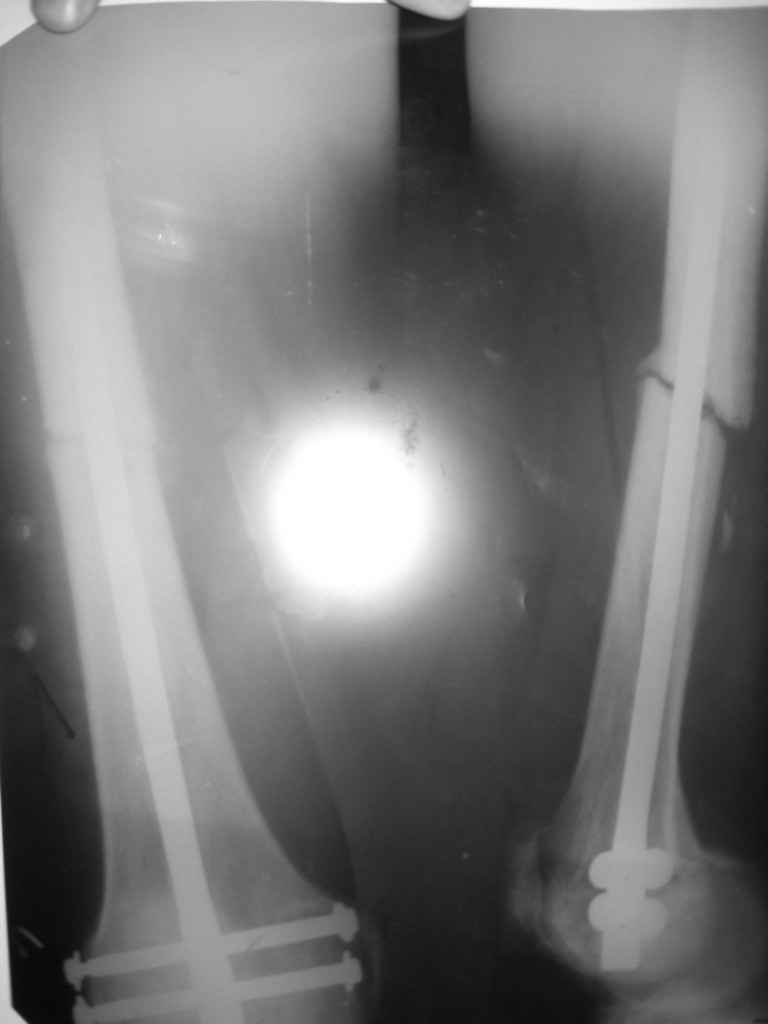

Уважаемые коллеги,обращаюсь к Вам за советом о дальнейшей тактие. Пециент был представлен к

Вашему вниманию 28 октября 2008 года. В декабре пациенту была выполнена динамизация стержня

удален винт из круглого отверстия).

В данный момент ( прошло 2 мес. с момента динамизации) наблюдается

диастаз в месте перелома и замедленная консолидация. Есть

несколько мнений по дальнейшей тактике:

1 убирать второй винт из овального отверстия и нагрузка, но не произойдет ротационное смещение в данном случае?

2 Переставить винт в "овальном отверстии" выше , что бы исключить

"ротацию", но не произойдет ли сминание кортикального слоя вблизи отверстия от удаленного ранее винта?

3 Дать долную нагрузку,и терапию направленную на стимуляцию

остеорегенерацию и посмотреть динамику, но не поломается ли винт в

овальном отверстии? Снимки прилагаются.